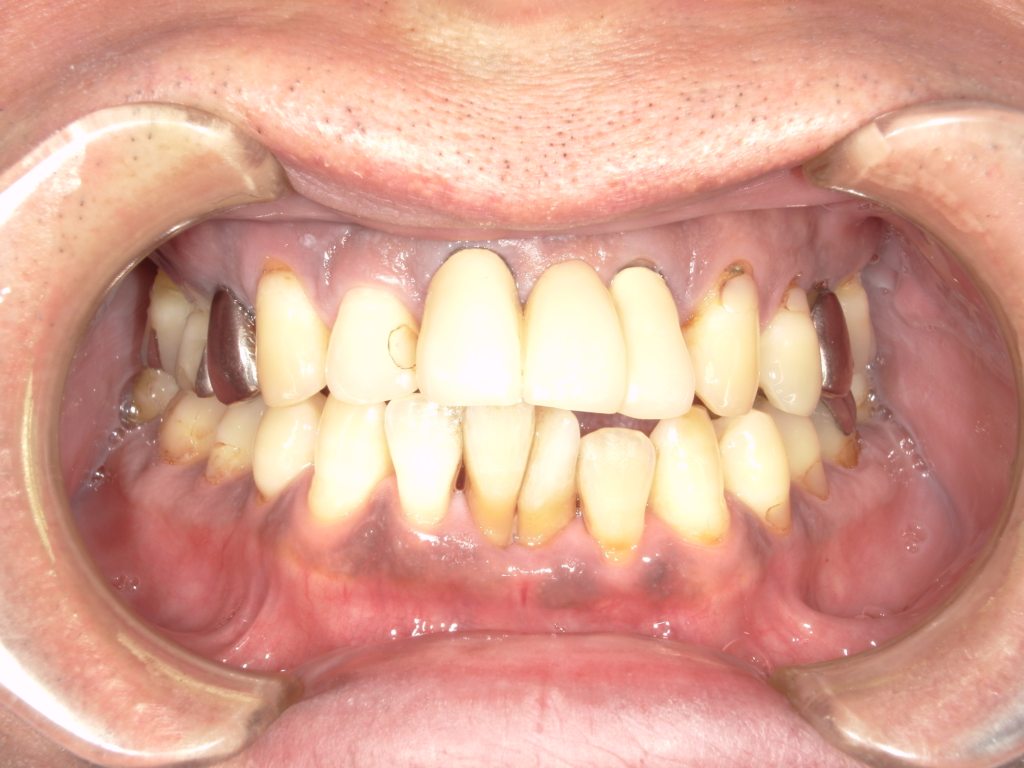

治療前

治療後